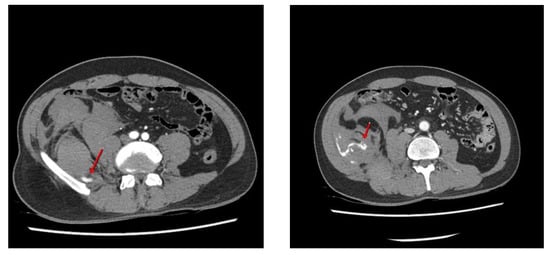

Figure 1. Although microscopic discectomy is still the mainstay of surgical treatment for symptomatic lumbar disc herniation, percutaneous disc nucleoplasty (PDN) is a new minimally invasive procedure for lumbar disc herniation. Given the current trends in minimal access surgery, PDN is considered a relatively safe and effective procedure and has been widely performed by spine surgeons [1,2]. A 38-year-old man presented with radiating pain in the left buttock and leg (S1 dermatomes) that started several months before visiting our outpatient clinic. Lumbar magnetic resonance (MR) imaging revealed central and left lateral-recess disc protrusion at the L5-S1 level. Percutaneous disc decompression using coblation technology (nucleoplasty) was performed in the angiography room, with the patient in the prone position under local anesthesia. A 17-gauge introducer cannula was introduced, using the posterolateral approach, into the identified disc level and advanced into the symptomatic portion of the disc under fluoroscopic guidance. The introducer needle was inserted into the L5-S1 disc, during which a failure to insert the needle resulted in several punctures of the lateral bone of L5. After the introducer needle insertion, the surgical probe was placed into the introducer needle and advanced until the probe tip contacted the annulus on the symptomatic side. Ablation was performed for 20–60 s and retreated four times to coagulate the intervertebral disc (L-disq®, U&I company, Uijeonbu, Korea). After the procedure, he reported a slight improvement in his left lower extremity symptoms. However, he complained of newly developed abdominal pain in the right flank region in the recovery room. Physical examination revealed tenderness and swelling in the right abdomen. Contrast-enhanced computed tomography (CT) of the abdomen and pelvis revealed an acute right retroperitoneal hematoma due to active bleeding caused by an L5 lumbar artery injury (Figure 1). Contrast-enhanced computed tomography images show high attenuation (arrows) from the right fifth lumbar artery within the hematoma, indicating active bleeding.